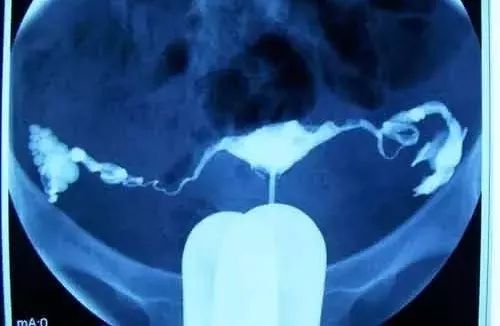

己经发生过宫外孕的女性,这说明她的输卵管通而不畅的可能性大,为了防止再次发生宫外孕,必须于宫外孕后三个月后或是想要孩子之前做一个输卵管造影检查,以确定输卵管的通畅程度。若是输卵管非常通畅,也无其它异常,则可以直接试孕。

输卵管造影▲

如果患过一次宫外孕而切除一侧输卵管,只要另一侧输卵管正常,还是有生育能力的。需要注意的是,再次怀孕后的早孕期就应进行B超检查,根据胚囊及胎儿心血管搏动所处位置,以排除第二次宫外孕,及时处理以保留输卵管。